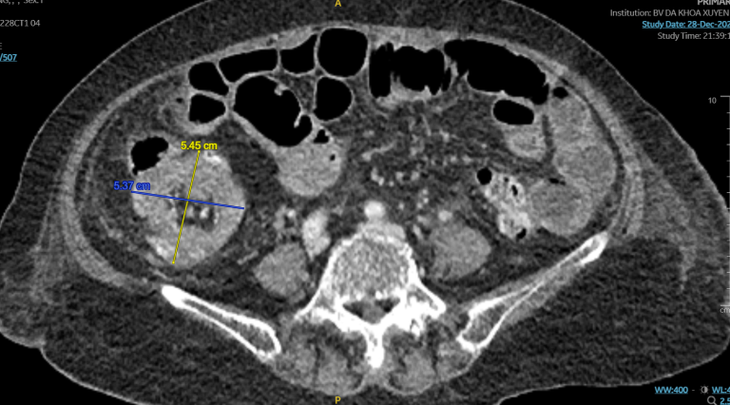

Hình ảnh khối u trên CT - Ảnh BVCC

Dựa trên triệu chứng bệnh, các bác sĩ nhận định đây là bệnh cảnh tắc ruột điển hình ở bệnh nhân lớn tuổi do khối u ống tiêu hóa. Người bệnh được chỉ định chụp CT-Scanner bụng chậu phát hiện một khối lồng ruột non vào đại tràng tại góc hồi – manh tràng, khối lồng hồi manh tràng do u có kích thước 5,45×5,37cm.